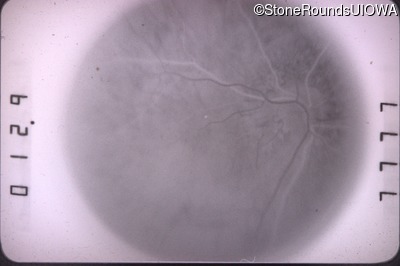

Fluorescein Angiography - Right - 20/60 -2

Exemplar